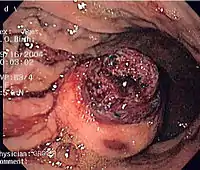

Endoscopic image of GIST in fundus of stomach, seen on retroflexion.

Same GIST seen on forward view of the endoscope showing overlying clot.